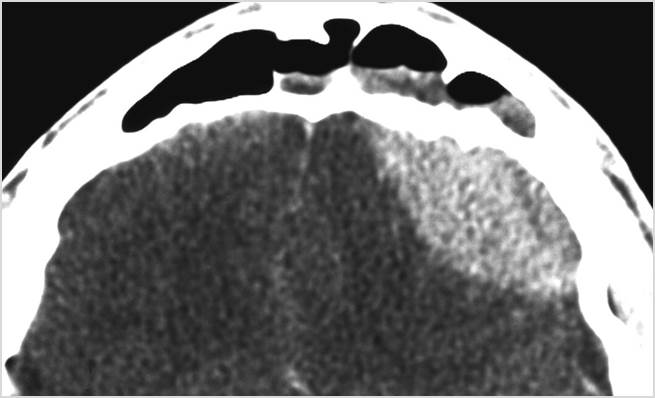

There is cerebritis specifically involving the frontal and temporal lobes. [Yes/No]

There is brain abscess specifically involving the frontal and temporal lobes. [Yes/No]